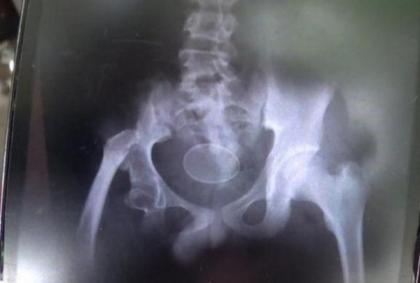

艾克马父母将他带到当地的萨雅客医院(Shaykh Yusuf Sungguminasa)检查,经过X光照射后,确实看到男童的骨盆腔及腹部内有外型极像鸡蛋的谜样物体;检查完毕后没多久,艾克马又在急诊室大出7颗。

▼经检查后,证实这些谜样蛋确实由男童体内产出。